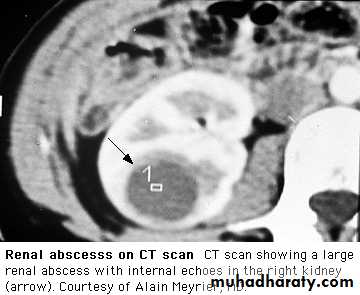

In perinephric abscess,there is marked pain and tenderness and often bulging of the loin on the affected side. Patients are extremely ill, with fever, leucocytosis and positive blood cultures. Urinary symptoms are absent, and urine contains neither pus cells nor organisms.